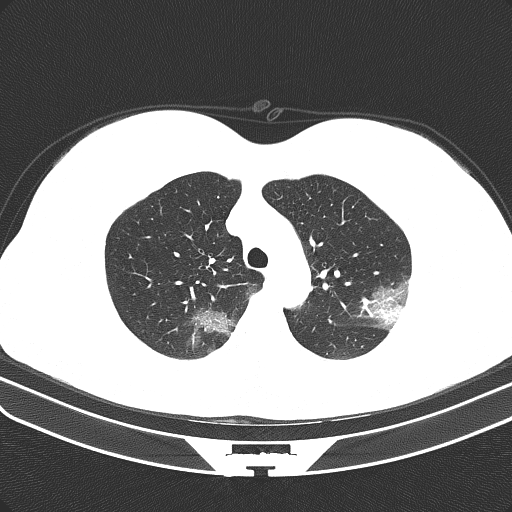

Figure 1 shows four CT scan slices, two from a non-COVID-19 CT scan, on the left and two from a COVID-19 scan, on the right. Bilateral ground glass regions are seen especially in lower lung lobes in the COVID-19 slices.

Some examples of CT slices from the cluster centers are given below. Figure 4 shows 10 consecutive slices from COVID-19 cluster center 0. Medical experts have annotated it as ’bilateral ground glass regions that appear, especially in lower lung lobes’. Figure 5 shows 10 slices from COVID-19 cluster center 2. According to medical experts’ annotation, this is consistent with ’COVID-19 pneumonia bilateral thickening filtrates’. Figure 6, on the contrary, shows 10 slices from non COVID-19 cluster center 9.